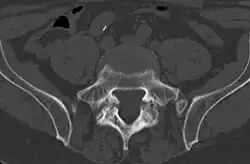

Computed tomography

Commonly known as a CT Scan or CAT scan, this form of imaging is very similar to x-ray technology but produces many more images than an x-ray does. The multiple images produce cross-sectional views not possible with an x-ray. This allows a physician or radiologist to examine the images from many more angles than an x-ray allows. For this reason the CT scan is much more accurate in detecting spondylolysis than an x-ray. Bone scintigraphy combined with CT scan is considered the gold standard which means that it is best at detecting spondylolysis.[15][17]